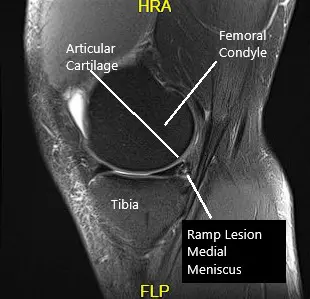

MRI examination of the left knee suggested a complex tear of the posterior horn of the medial meniscus. Small horizontal cleavage tear of the body of the lateral meniscus.Moderate joint effusion with synovitis.

MRI of the knee in the sagittal and coronal section.